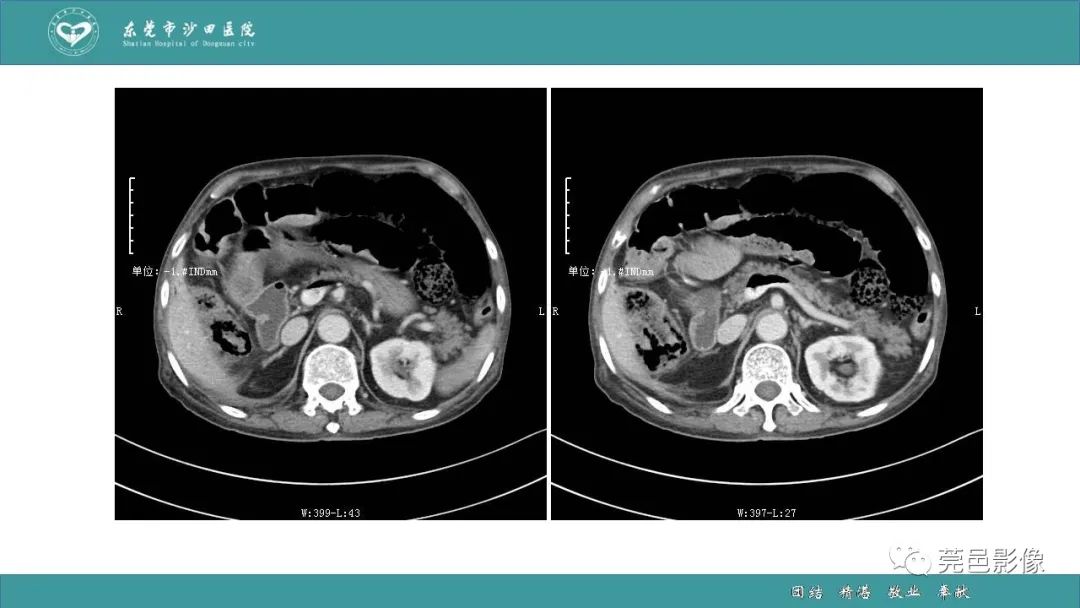

1例肠缺血坏死伴门静脉积气的CT诊断